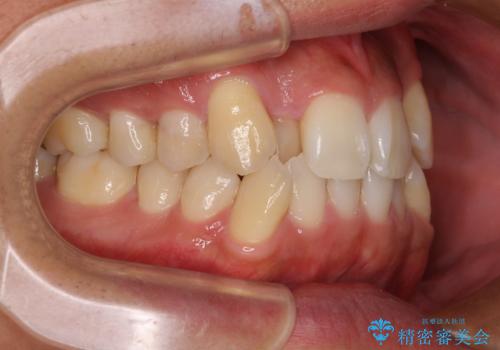

上下の前歯部に強い叢生(ガタガタの歯並び)があり、そのまま歯を並べると出っ歯になってしまう可能性がありました。

そこで、上下左右の第一小臼歯を抜歯し、歯が並ぶためのスペースを確保し叢生を解消する治療計画を立てました。

八重歯はきれいに整い、前歯もバランスよく収まり、横顔のラインも自然に改善されました。